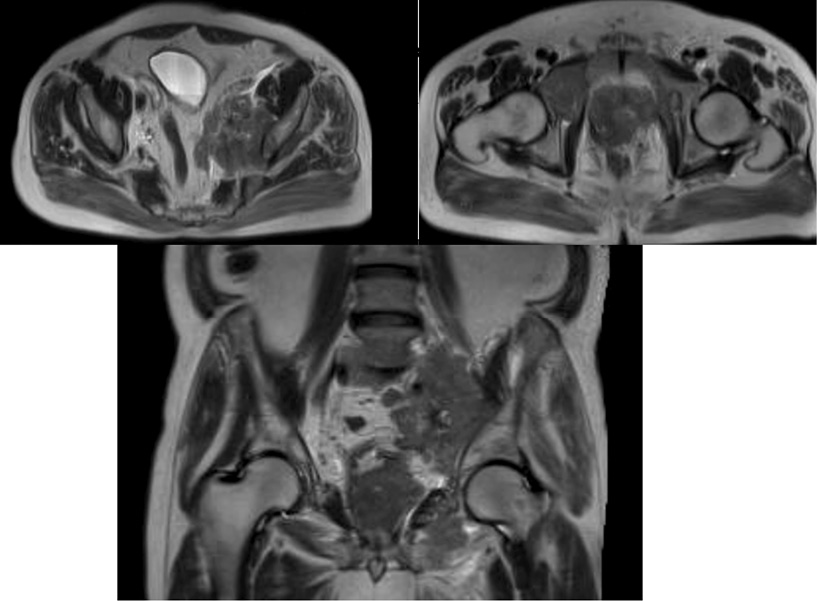

- По данным магнитно-резонансной томографии (МРТ) – новообразование левой доли ПЖ 45×44×36 мм. Слева, вдоль подвздошных сосудов – конгломерат лимфатических узлов, 70×44 мм с муфтообразным окружением подвздошных сосудов.

Рис. 6. МРТ через 2 мес от начала лечения. Отмечается увеличение размера конгломерата подвздошных лимфоузлов слева (левый верхний и нижний слайд), экстракапсулярное распространение опухоли ПЖ без вовлечения прямой кишки и мочевого пузыря (правый верхний слайд).